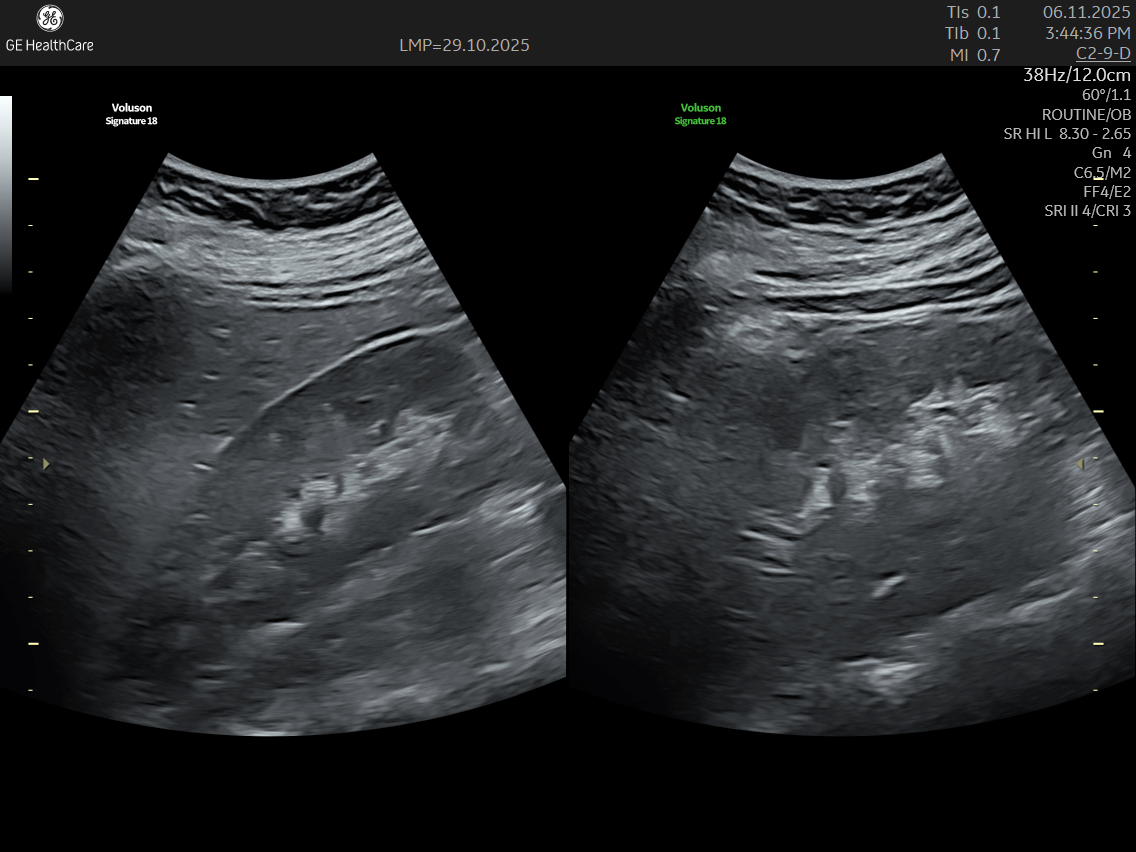

IMAGE GALLERY